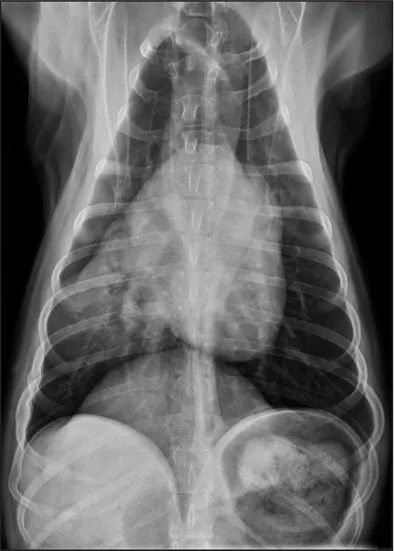

CASE 1.1 A 7-year-old neutered male Labrador Retriever who was hit by a car. You obtain these thoracic radiographs: Figs. 1.1a, b, left and right lateral projections, respectively; Figs. 1.1c, d, ventrodorsal and dorsoventral projections, respectively.

1.1d